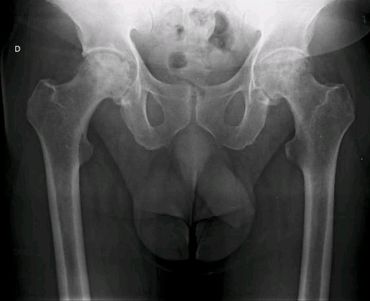

Artroplastía total de cadera izquierda